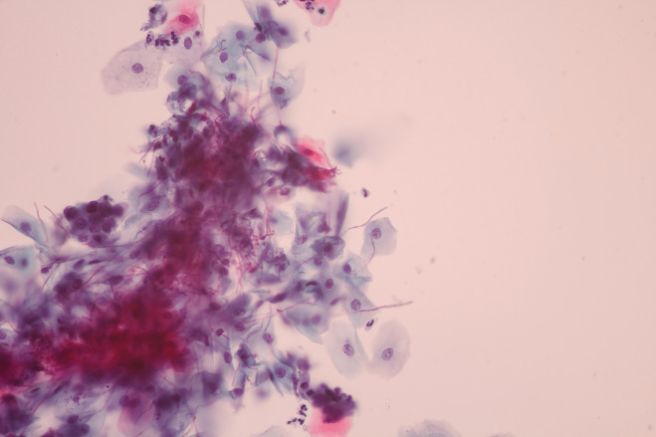

염증수치가 높게 나타나는 가장 대표적인 이유 중 하나는 감염성 질환입니다. 세균, 바이러스, 곰팡이, 기생충 등 외부에서 침입한 병원체가 체내에 들어오면, 몸은 이를 제거하기 위해 면역 반응을 일으킵니다. 백혈구가 활성화되고, 염증을 조절하는 여러 단백질과 사이토카인이 분비됩니다. 혈액 내에서 염증을 나타내는 수치인 CRP나 ESR이 상승하게 됩니다.

감염성 질환의 경우 염증 반응은 침입한 미생물을 억제하기 위한 방어 작용이지만, 반응이 과도하면 전신으로 염증이 확산될 수도 있습니다. 발열, 근육통, 피로감 등이 동반되는 경우가 많으며, 감염 부위에 따라 다양한 신체 변화가 나타날 수 있습니다.